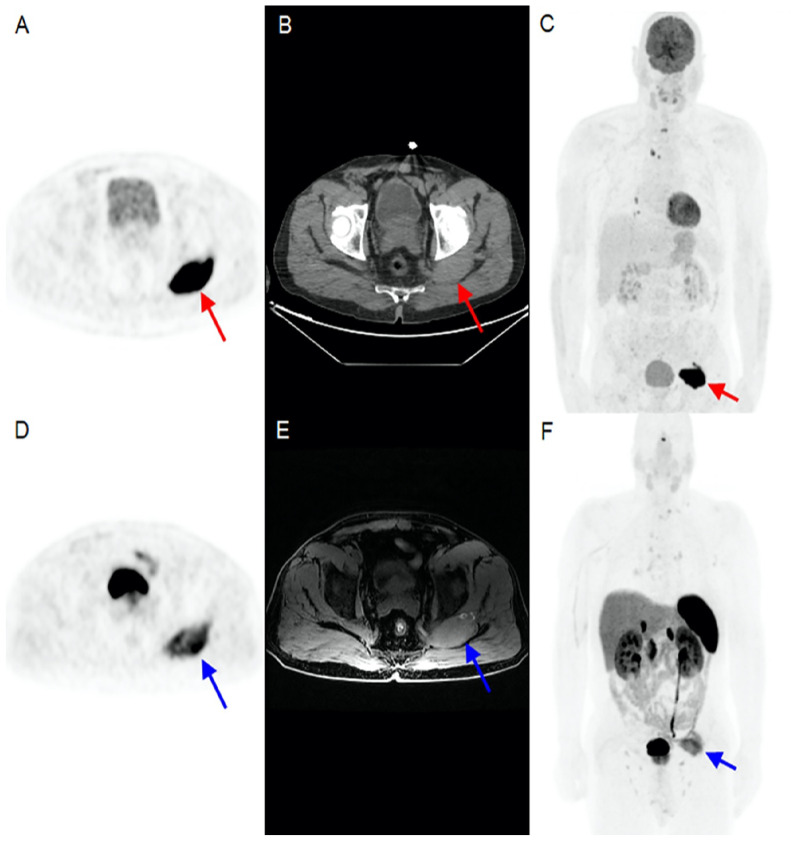

A 56-year-old male patient underwent total thyroidectomy, and pathology revealed multicentric papillary thyroid cancer. His post-operative stimulated thyroglobulin value was >500 ng/mL. 18F-fluorodeoxyglucose positron emission tomography (PET) computed tomography revealed hypermetabolic metastatic pulmonary nodules, cervical, and mediastinal lymph nodes. There was also a hypermetabolic lesion in the left gluteal muscle. Due to the patient's history of a pilonidal cyst in the same region, the possibility of an abscess was also considered, and due to the absence of radioactive iodine (RAI) uptake in the lesion, follow-up was deemed appropriate. During follow-up, as the patient progressed to RAI-refractory state, 68Ga-DOTATATE PET/magnetic resonance imaging, which was done for radionuclide therapy planning, revealed heterogeneously increased uptake in the gluteal lesion. A subsequent biopsy confirmed the diagnosis of PTC metastasis.